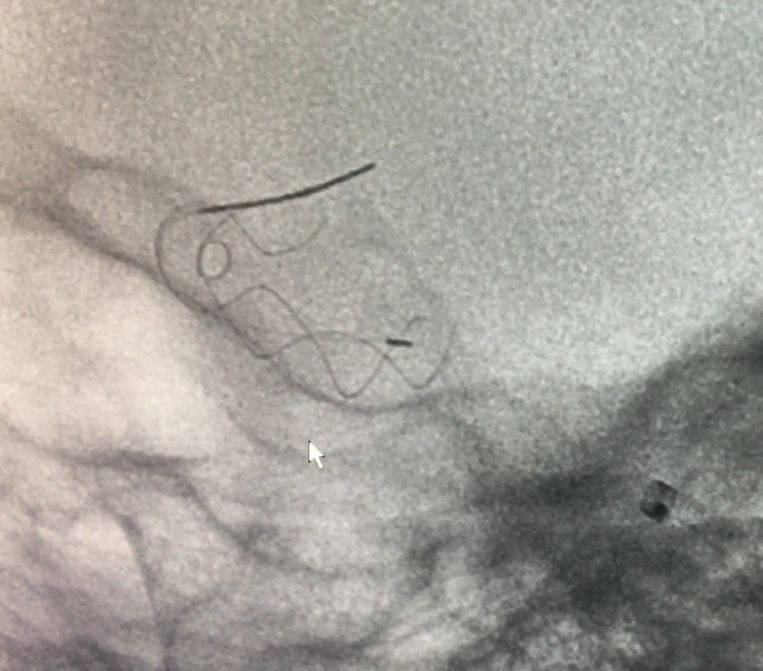

锚定后,整体回撤至合适位置后,通过张力释放法缓慢释放支架,直至支架完全打开。观察见支架贴壁良好,动脉瘤颈完全覆盖,遂完全释放支架。

全脑DSA正侧位造影示血流通畅。

动脉瘤内造影剂滞留,未填弹簧圈。行Xper CT,观察见支架完全打开,贴壁良好。术程顺利结束。